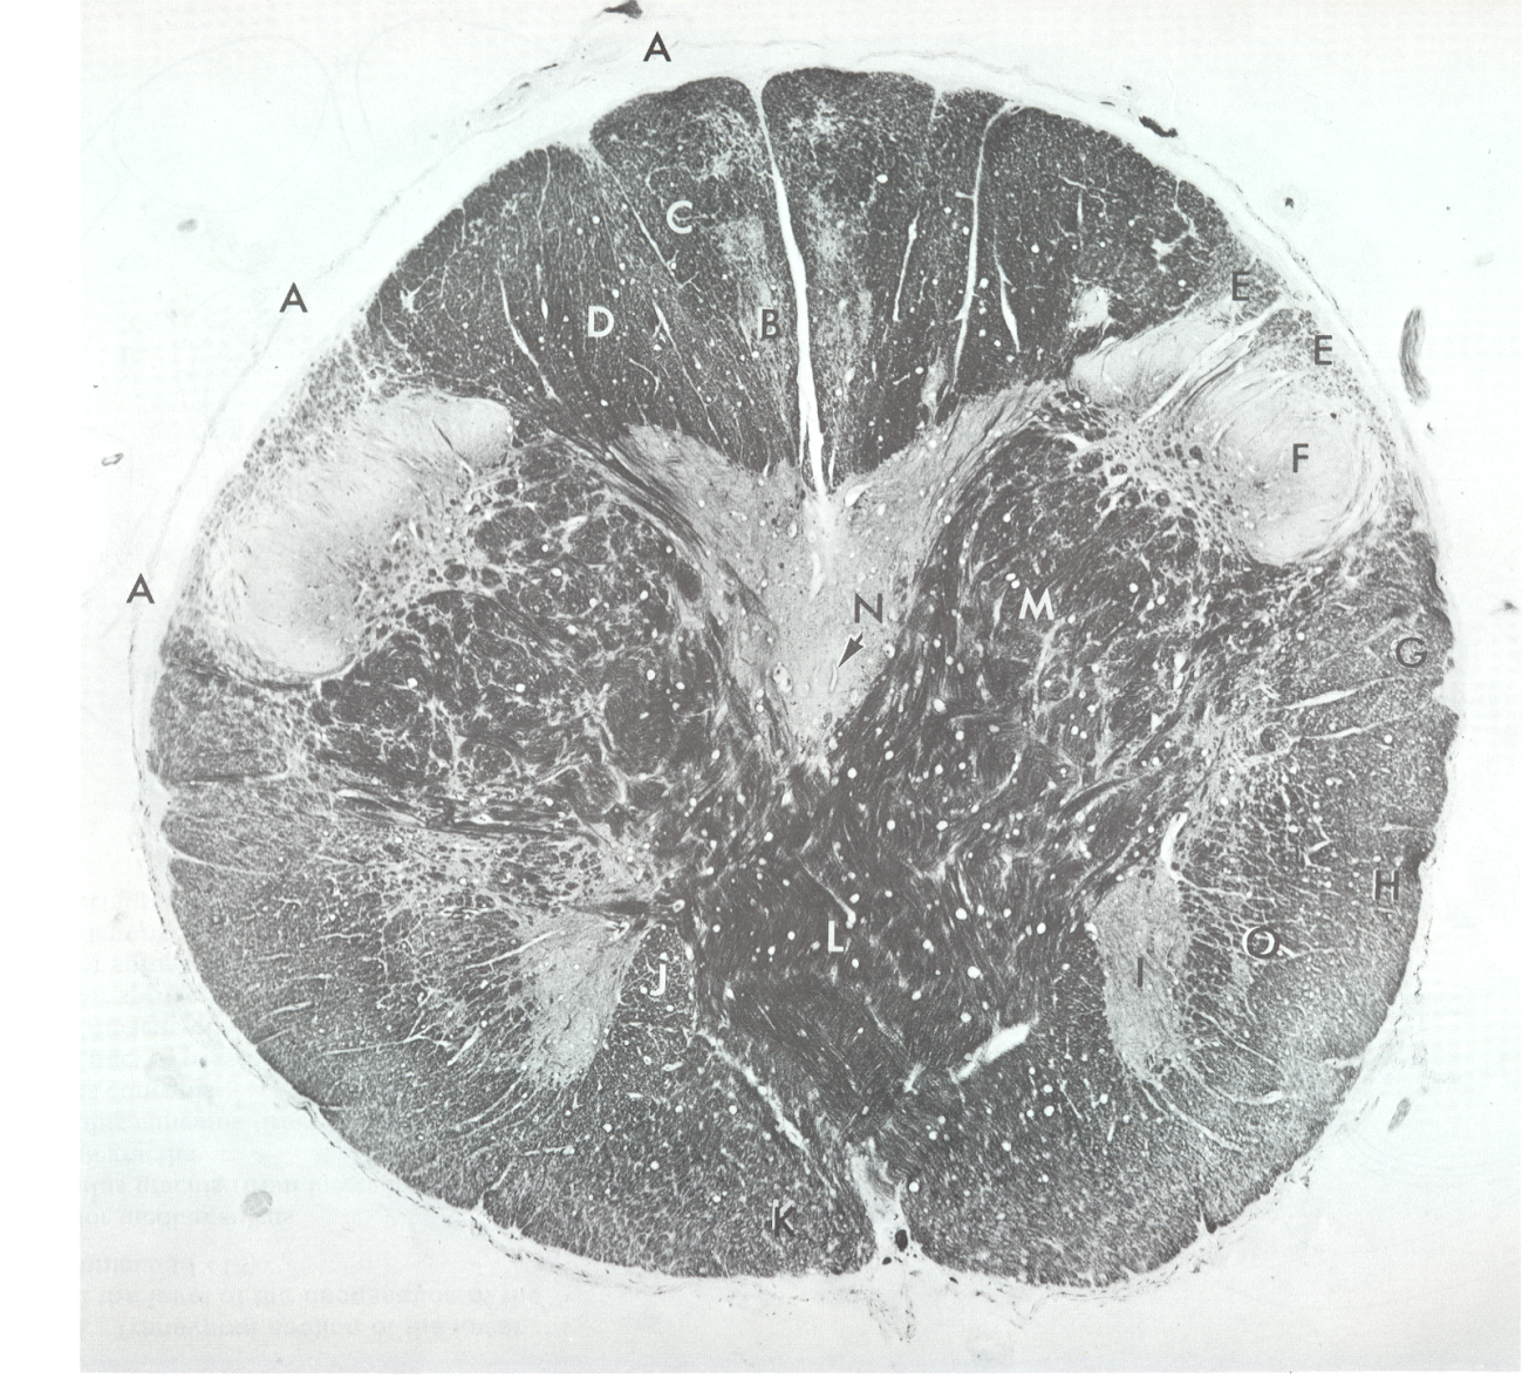

b

nucleus gracilis

c

fasciculus gracilis

d

fasciculus cuneatus

e

spinal tract CN V

f

spinal nucleus CN V

g

posterior spinocerebellar tract

h

anterior spinocerebellar tract

L

pyramidal decussation

m

lateral corticospinal tract

o

spinal lemniscus